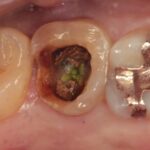

精密根管治療により、

歯を残せる可能性を最大限に

当院ではCT・マイクロスコープ・セファロなどの精密検査機器を活用し、歯を残すための選択肢をできる限りご提案します。

歯髄温存治療(MTA)や歯冠長延長術、矯正的挺出など、専門的な治療にも対応。

また、痛みに配慮した麻酔方法で、安心して治療を受けていただけます。

歯を残すための精密診断と専門治療

MTAによる歯髄温存治療に対応

表面麻酔・極細針で痛みを最小限に